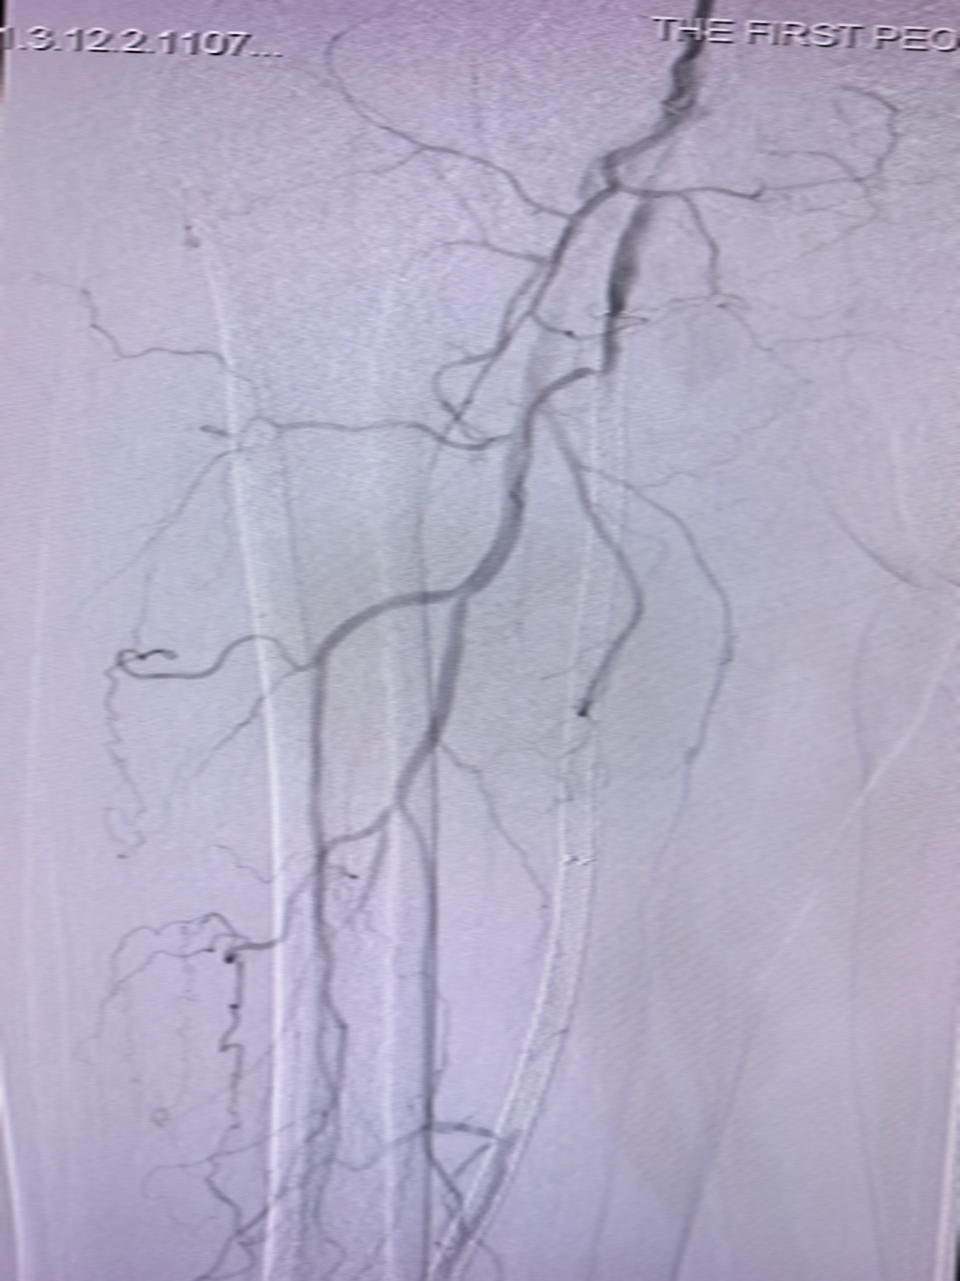

1.术前造影:股浅动脉及支架狭窄闭塞

经过精心准备手术如期开展。介入与血管外科团队在DSA血管造影机引导下,严格按照操作流程,高速旋切及清除血管、支架各处的斑块等阻塞物,经过1小时操作,斑块清除彻底,闭塞血管成功开通,恢复血流。术后,患者足趾颜色马上从紫绀变回红润,皮肤温度也恢复正常,手术取得圆满成功。